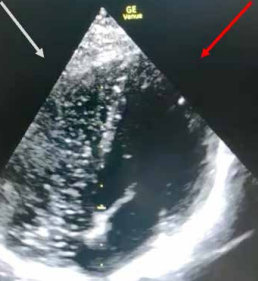

Konsultation durch einen Kardiologen. Hier bestätigt sich

die Verdachtsdiagnose eines ausgedehnten Hebungsinfarkts

der Herzhinterwand

(Abb. 1). Es erfolgt die rasche Indikationsstellung für eine

Koronarangiographie (Herzkatheteruntersuchung), die nur

nach intensiver Rücksprache und Drängen durch die

Hotline-Ärzte bei mangelnder zeitlicher und personeller

Verfügbarkeit zeitnah und nicht wie ursprünglich avisiert

in sieben Tagen erfolgen konnte. Im Rahmen der

Koronarangiographie bestätigte sich der langstreckige

Verschluss einer Herzkranzarterie, die mittels Stents

wieder eröffnet wurde. Diese Intervention rettete dem

Kunden das Leben. Der Kunde und die aqua med-Hotline

Abb. 1: Exemplarische Darstellung eines 12-Kanal-EKGs. Deutliche ST-Streckenhebungen über der Herzhinterwand zu sehen in den Extremitäten-Ableitungen II, III und AVF (blauer Pfeil). Der Übersicht halber wird auf die Darstellung der Brustwandableitungen verzichtet. © Dr. Dr. Philipp Stahl